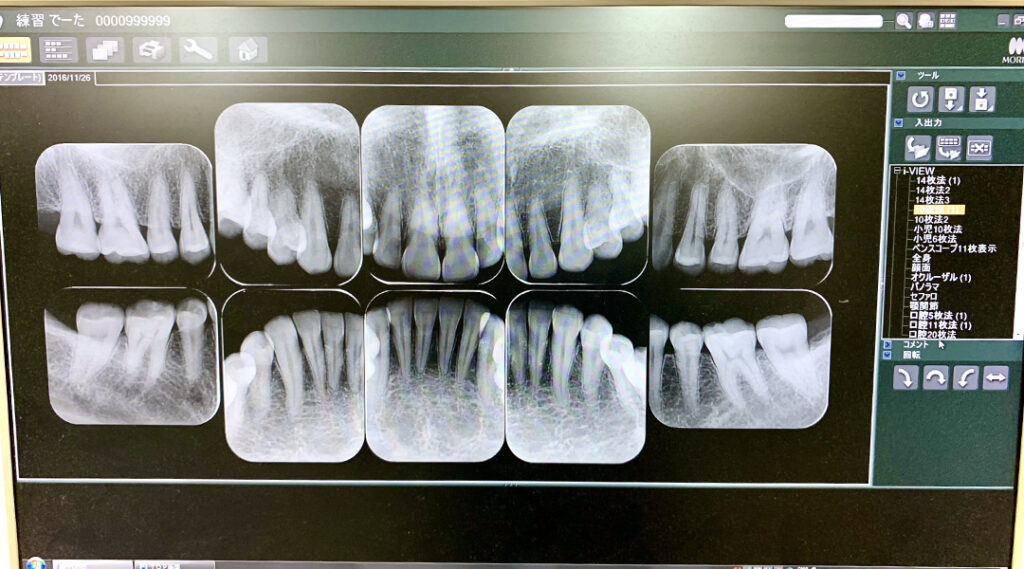

今月は、当院で行っている【歯周病治療】についてお伝えします。歯周病は「歯肉が腫れる」症状を知っている方が多いようです。それ以外に、「歯を支えている歯槽骨が吸収する(無くなる)」ことを知って欲しいです。なぜなら、その骨が吸収する時に、自覚症状がないまま進行するからです。だから、歯科で『早期発見』することが、何よりも歯周病を予防するのに大切です。その骨の吸収状態を調べる為に、当院では、先ず『全ての歯を10枚から14枚の小さいレントゲン』で撮ります。この撮影法の利点は、歪みが少なく精度の高い撮影ができるので、骨の吸収度を診る以外にも、小さな虫歯なども診断できます。